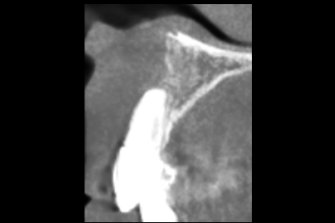

上唇の腫脹を認め、CT検査にて根尖部に嚢胞様透過像を認めた。左上の前歯が不自然に大きく噛み合わせが強くなっていたことがフレアアップの一因と考える。精密根管治療を行い、感染経路を遮断したのち歯根端切除術にて嚢胞を摘出した。

治療中